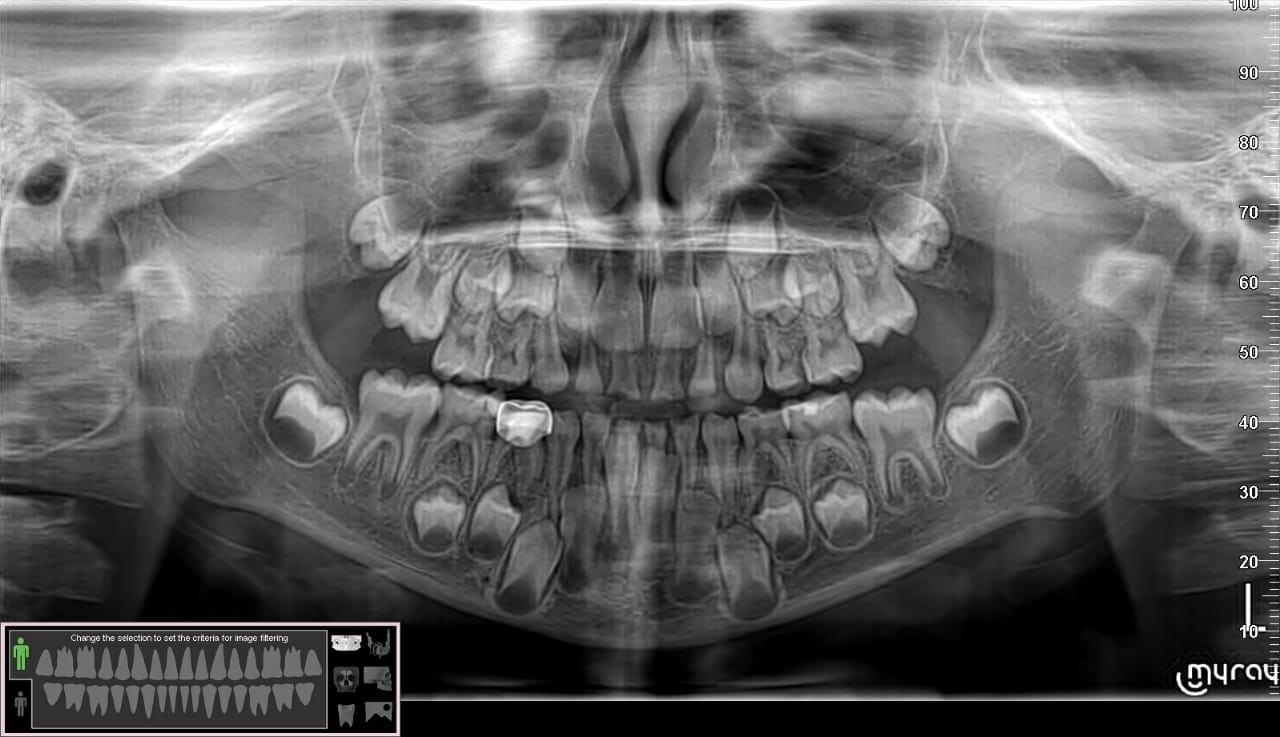

Pediatric filling is a medical procedure aimed at treating tooth damage resulting from caries. Filling is done by removing the damaged part of the tooth and filling the cavity causing this damage using special medical materials that contribute to restoring the tooth’s function and aesthetic appearance.

Fillings for children is a medical procedure aimed at treating tooth decay and restoring damaged teeth to their natural state, and there are several advantages of fillings in children that make them important and necessary, including: